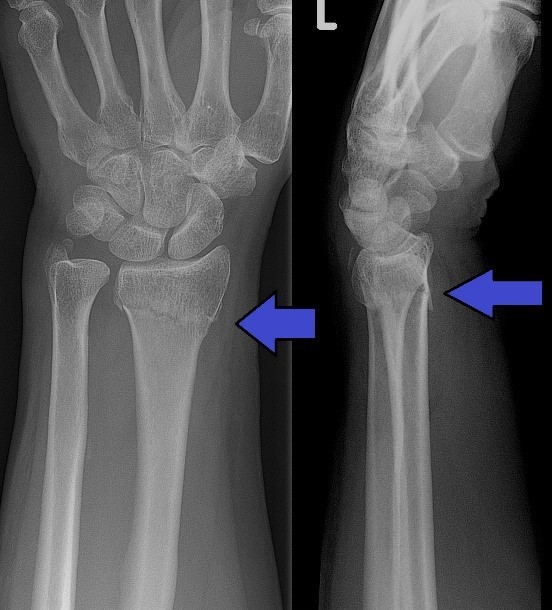

What fracture is this?

Colles Fracture

What is shown on XR in a Colles Fracture?

Displacement of radius and radial impaction leading to shortening